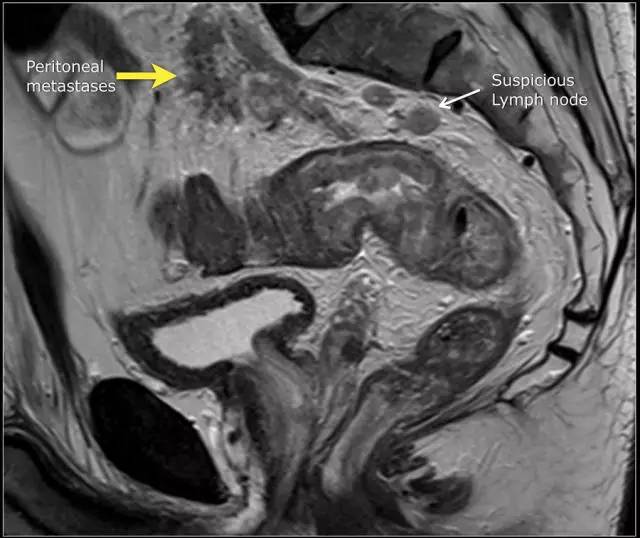

图 15 同一患者腹膜转移的矢状图(箭头),在直肠内还有可疑的淋巴结